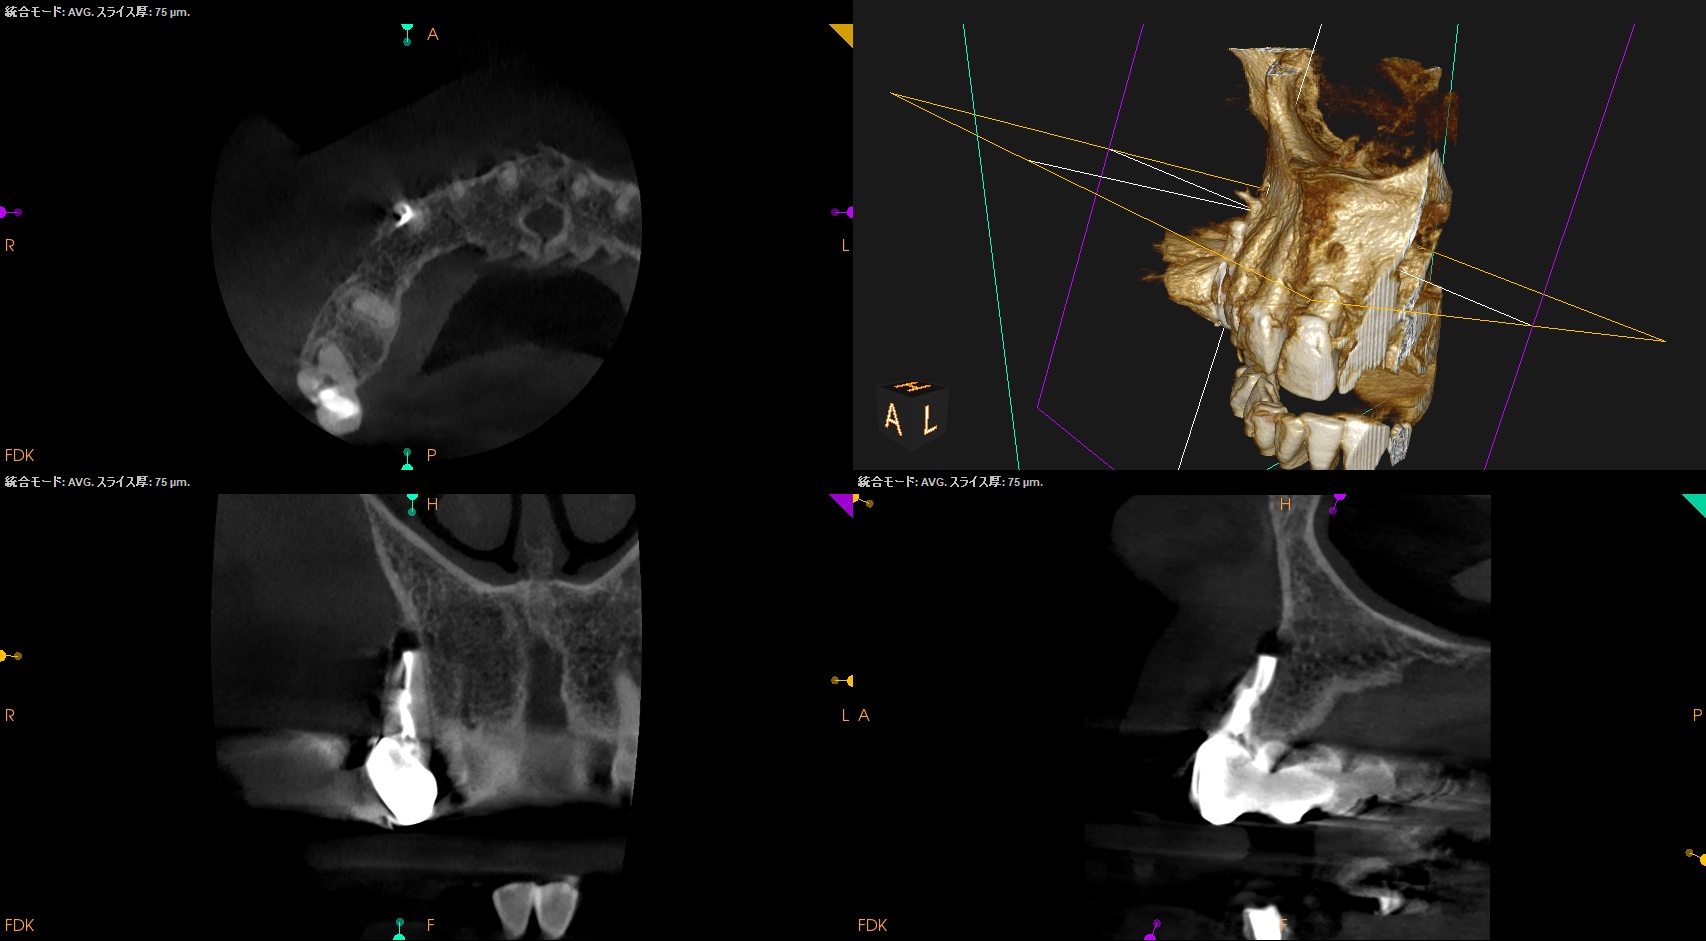

PA, CBCTを撮影した。

しょっぱい逆根管形成になったが主根管は確保されたので縫合して終了した。

根切した部分にはだいぶ骨が添加されているし、外部吸収も進展していないようだ。

ということでこの処置にはこれからも定期的な経過観察が必要である。